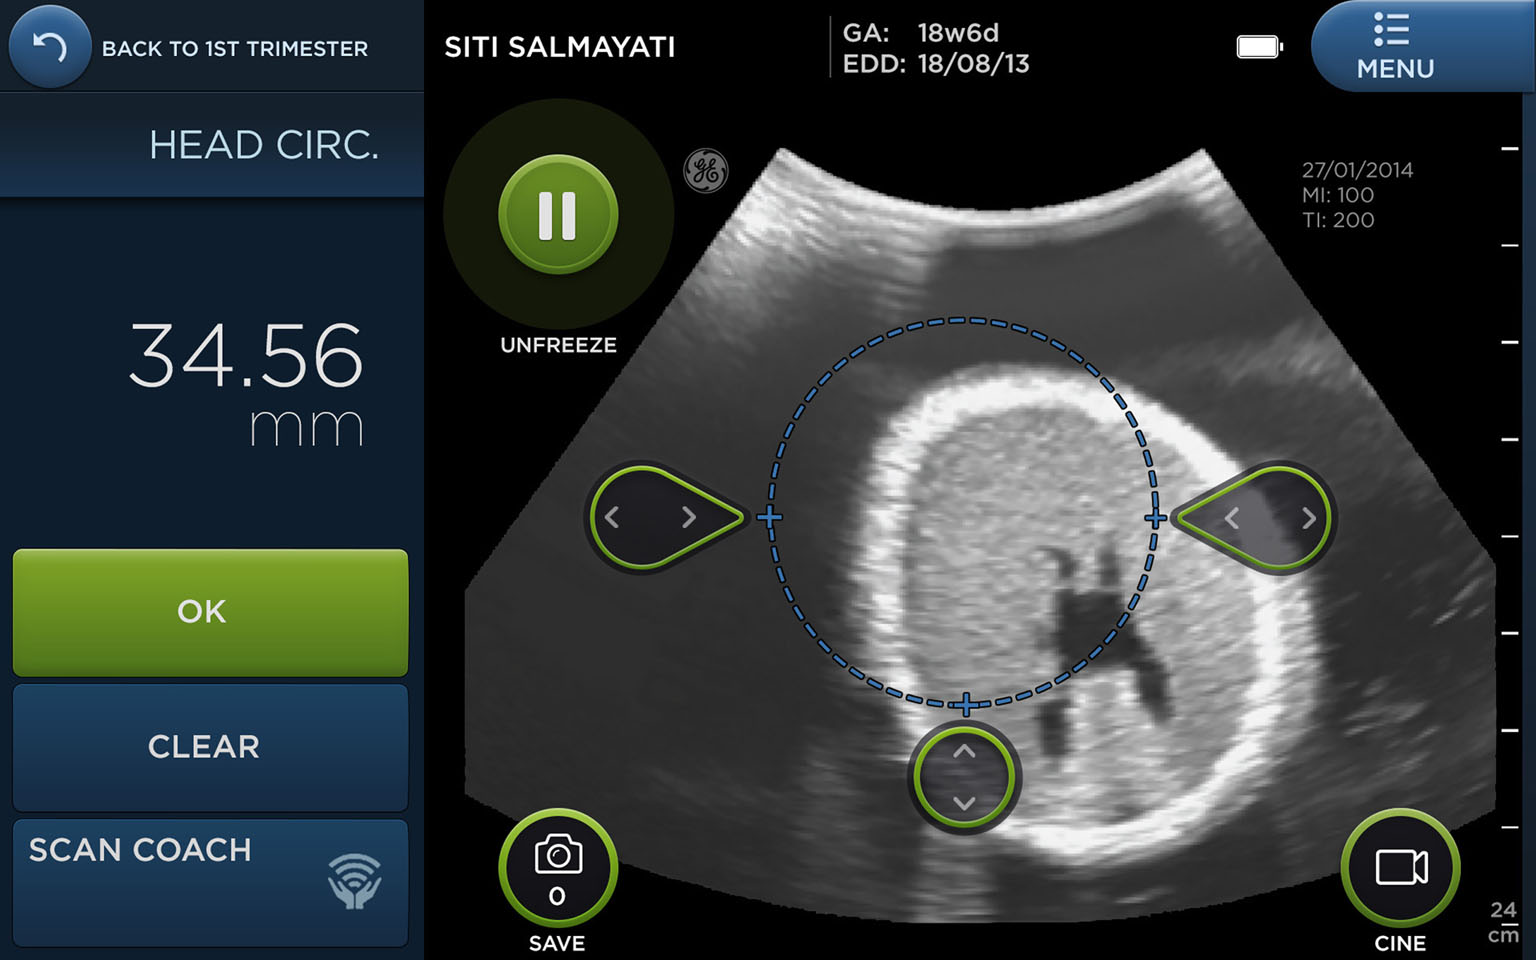

The user interface of the Vscan Access employs design elements that make it look friendly, yet professional, and also easy to use. Field studies have shown that the detection rates of potentially life-threatening conditions in pregnant women improved two-fold when the device was used.

The colour scheme and fonts were chosen to make it look friendly, yet professional, said Mr Jabry, and there are clear buttons that users know they can press and on-screen "calipers" they can drag around with their fingers to measure distances in the ultrasound image.

But beyond looking nice, Mr Jabry explained that the software also guides the user through the correct sequence of steps from beginning to end, and shows sample images to help the user get the correct scan.